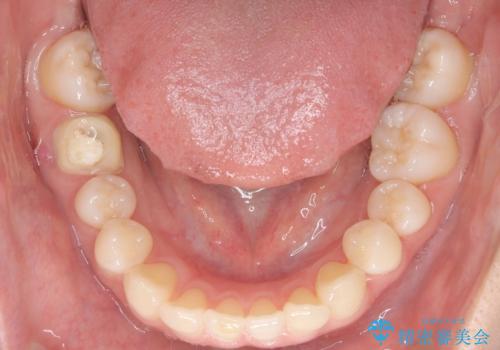

非抜歯矯正で八重歯を改善|短期間8か月で美しい歯並びに|インビザラインライト上顎のみで矯正

- 「八重歯を治したい」との主訴でご来院された患者様です。。

非抜歯で上顎のみインビザラインライトを使用して矯正を行いました。

短期間(約8か月)の治療で歯並びが整い、患者様も大変喜ばれました。